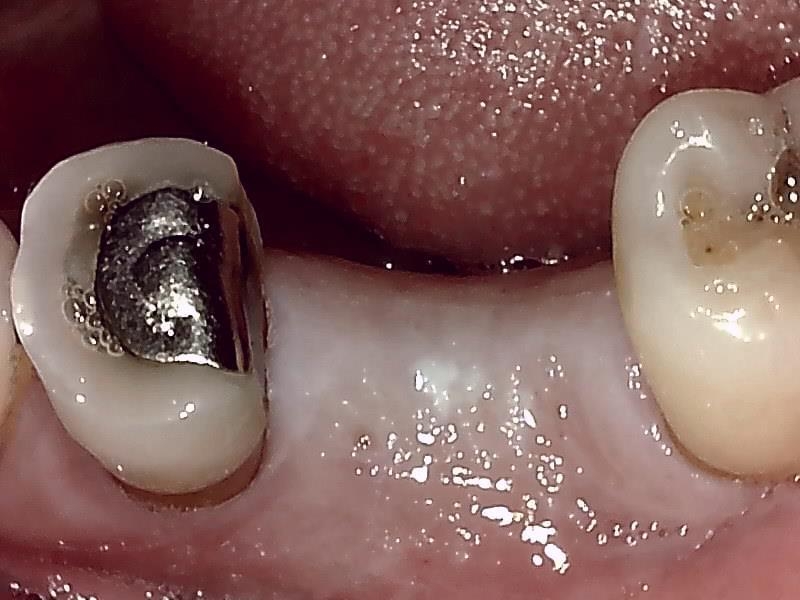

術前の顎堤

顎堤歯肉をくり抜き切開して歯肉片を温存する。